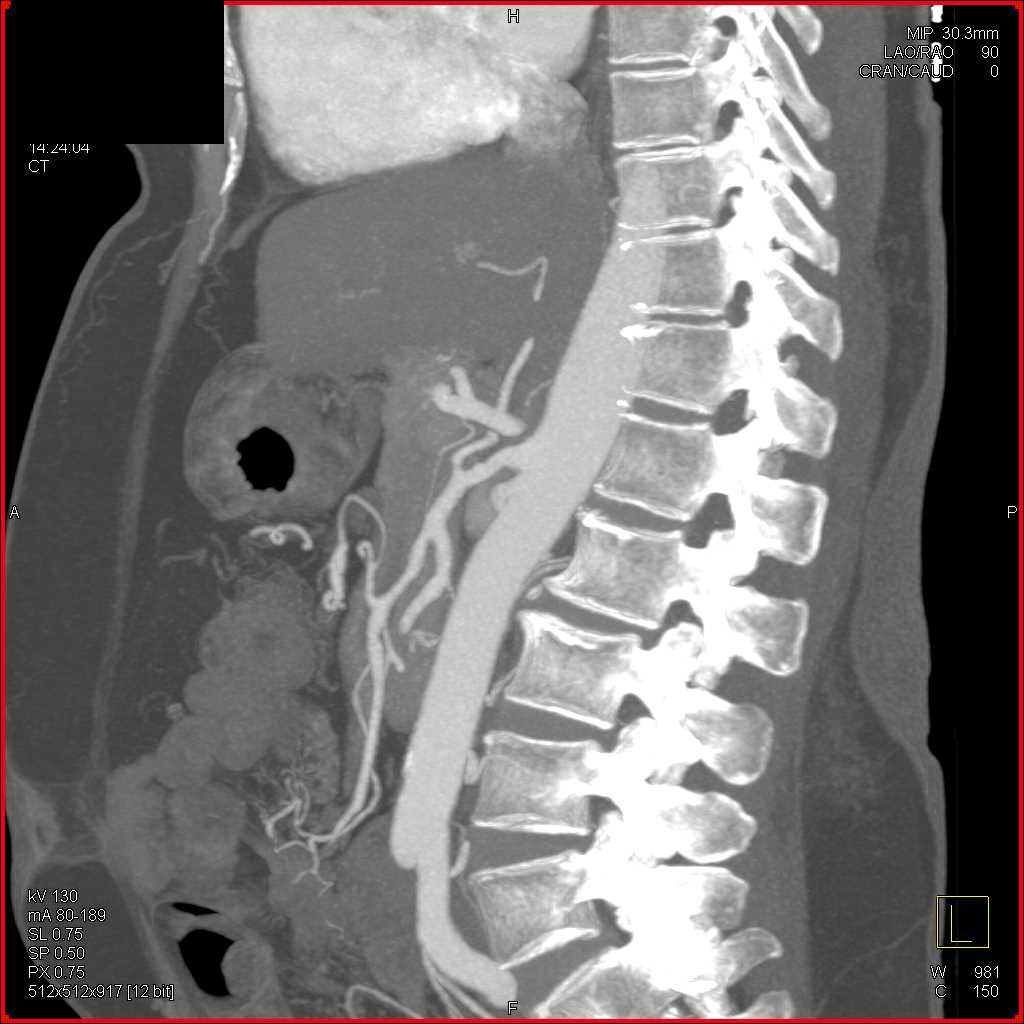

Neuroendocrine Tumor Body of Pancreas